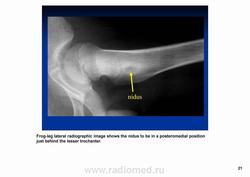

Остеоидная остема.

Диагностика и дифференциальная диагностика.